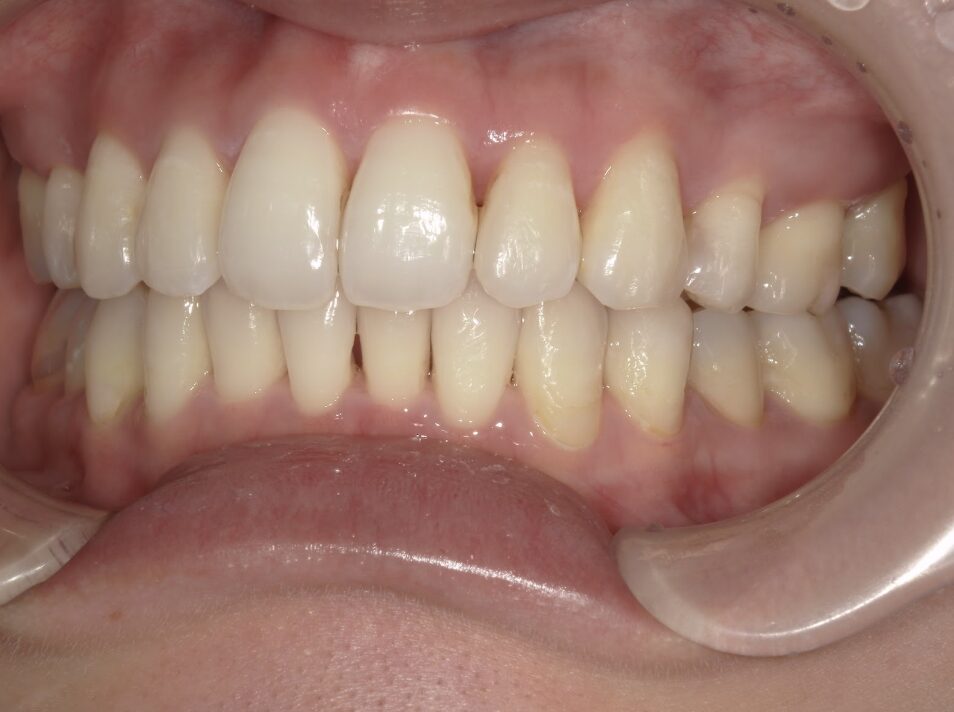

治療後

前歯が全く当たっていないを主訴に当院を受診され、開咬・上顎前突・下顎叢生を認めました。

上顎左右4番抜歯を行いIPRを使用してマウスピース型矯正装置(インビザライン)を使用し、改善を行いました。

治療期間1年9ヶ月